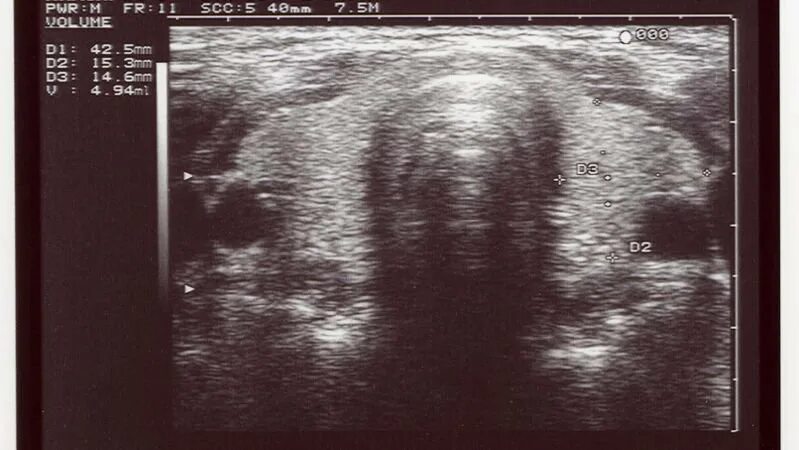

Записаться на узи щитовидной железы